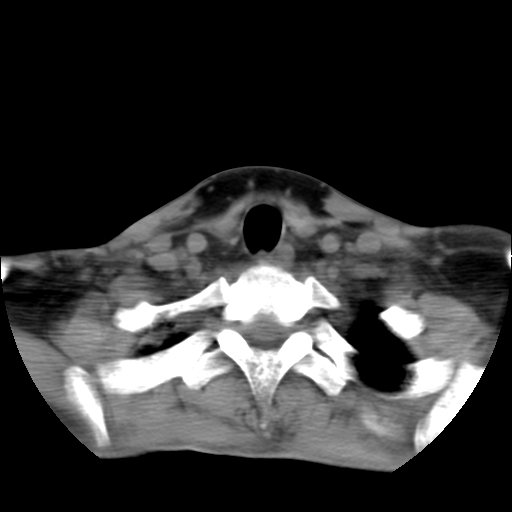

标题: CT24019:男,45岁,发现颈部肿物5个月。 [打印本页]

标题: CT24019:男,45岁,发现颈部肿物5个月。

男,45岁,发现颈部肿物5个月,彩超示:双侧颈部及下颌部软组织增厚。

考虑双侧颈项部良性对称性脂肪增多症。